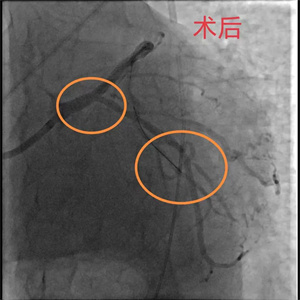

关键时刻,心血管内科副主任医师吴义权、主治医师孙春根、夏秋旺和介入团队紧密协作,在IABP的保护下快速开通血管。术后,患者转入心血管内科监护病房。在医护团队的精心医治和悉心照料下,现已平安出院。